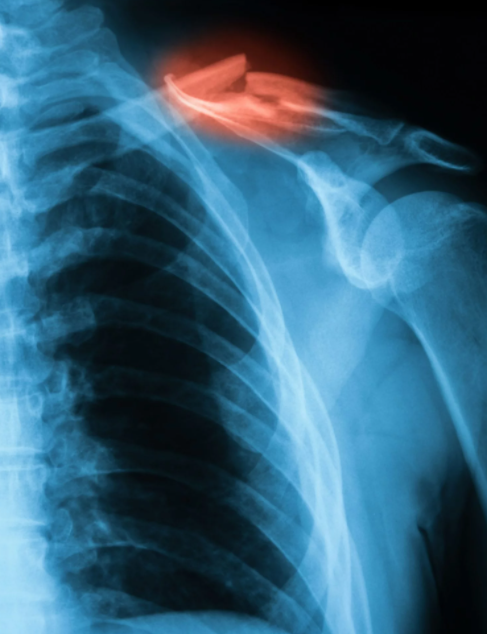

▣ 석회 성 건염

석회 성 건염의 원인을 확인할 수는 없지만 상당히 고통스러울 수 있습니다. 칼슘 침착 물이 근육이나 힘줄에 축적되는 상태로 석회 성 건염을 설명합니다. X- 레이로 볼 수 있으며 일반적으로 30세 이상이지만 모든 연령에서 발생할 수 있는 사람들에게 더 흔합니다.

석회 성 건염은 일반적으로 항염증제 나 주사로 치료할 수 있으며, 치료 없이 시간이 지나면서 해결되는 경우도 있습니다. 그러나 너무 심하면 수술이 필요할 수도 있습니다.